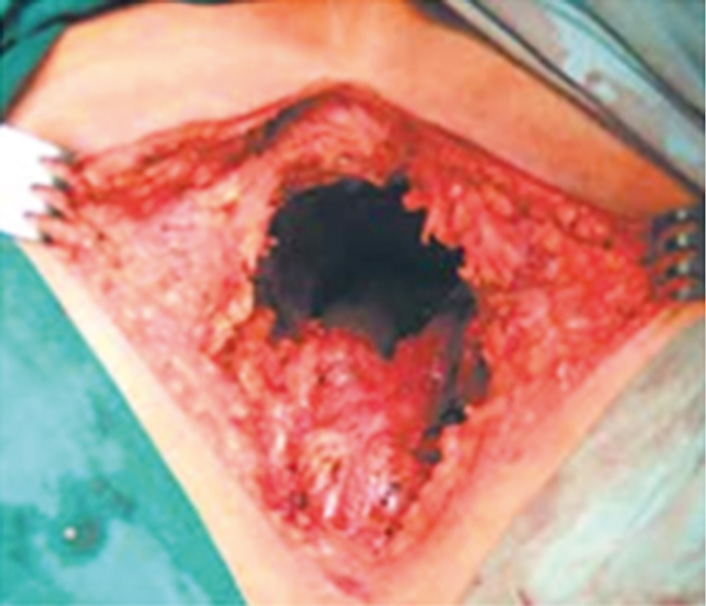

Согласно методике ЭлБПЭ на промежностном этапе операции диссекция осуществляется снаружи мышц, поднимающих задний проход, с пересечением у места их прикрепления к костям таза (рис. 4). Из-за цилиндрической формы препарата в литературе встречается название «цилиндрическая ЭлБПЭ». Рак нижне- и среднеампулярного отделов прямой кишки размером T3 и Т4 считают весомым показанием для ЭлБПЭ. Сейчас ЭлБПЭ достаточно широко применяют в ведущих клиниках всего мира. Некоторые авторы предлагают во всех случаях БПЭ выполнять экстралеваторную диссекцию [66, 67]. В последние годы исследования показали, что ЭлБПЭ улучшает результаты лечения онкологических заболеваний, таких как рак прямой кишки дистальных локализаций, в сравнении с показателями при стандартной БПЭ. Однако в результате экстралеваторной диссекции часто образуется обширный дефект промежности с необходимостью пластического закрытия (рис. 5).

Рис. 5. Промежностная рана после экстралеваторной брюшно-промежностной экстирпации прямой кишки. Наблюдение и фотография А.М. Карачуна (Национальный медицинский исследовательский центр онкологии им. Н.Н. Петрова, Санкт-Петербург, 2014 г.)

Fig. 5. Perineal wound after extralevator abdominoperineal excision. Observation and photography by A.M. Karachun (N.N. Petrov National Research Center of Oncology, Saint Petersburg, 2014)